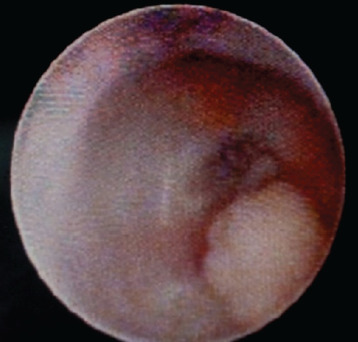

Background: The presence of blood in breast milk gives it a rusty or brownish color, which is referred to as "Rusty Pipe Syndrome (RPS)".

Results: Six women aged 25 to 36, experienced RPS during breastfeeding. The majority of them had no previous birth history (83%), were primigravida (83%) and had bilateral presence of blood in the milk (67%), with symptoms appeared on the second postpartum day (50%).

Conclusion: Based on extensive studies and literature reviews, RPS is generally considered a benign condition, typically presenting bilaterally. However, unilateral cases, such as those observed in our study, are rare.